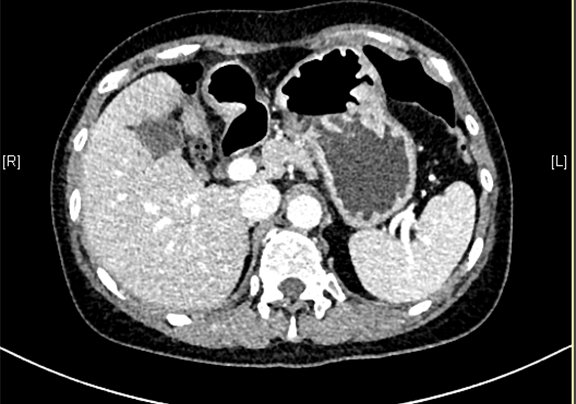

肝细胞肝癌伴坏死-CH-001-LT-000344

一般情况:CH-001-CT-000344,60岁男性,身高152cm,体重52kg,

主诉:查体发现肝血管瘤1天。

现病史:患者于1天前于当地医院查体发现肝血管瘤,无腰背部放射痛、皮肤巩膜黄染、恶心、呕吐、寒战、高热、腹泻、血便、咳嗽、咳痰、胸闷、气短、尿频、尿急、尿痛、血尿。患者自发病以来,精神状况良好,食欲可,睡眠良好,大便正常,小便正常,体重无明显变化。

下腹部增强CT示:肝左外叶肝癌可能性大; 肝左内叶及右后叶海绵状血管瘤可能性大。

肿瘤标志物:AFP>1210.00ng/mL CEA2.39ng/mL CA19-98.58ng/mL CA12526.31ng/mL CA506.94ng/mL

模拟手术操作,自动计算切除肿瘤体积。肝脏体积为970.6ml,肿瘤体积为277.2ml,肿瘤体积为肝脏体积的28.6%,通过比对60-70岁正常肝脏体积为1262.7±284.31 ml,通过术前模拟手术,精准判断切除后剩余肝脏体积能耐受,避免肝衰竭发生。

术后病理提示1、(左外叶)肝细胞肝癌伴坏死,II-III级,范围9.5*5.5cm,以粗梁型及实片型生长方式,侵及局部肝被膜,未累及肝断端;脉管癌栓(+,M1),神经侵犯(-),未见确切小胆管内癌栓及胆管壁侵犯,肿物周围未见卫星结节。2、慢性肝炎,G2S3。手术顺利,术后给予抑酸、补液、抗感染及对症支持等治疗,现患者术后恢复可,于2016-7-26出院。

随访5月复查CT,肝左外叶术后改变;肝左内叶及右后叶斑片状稍低密度影,较前未见明显变化。

术前CT检查:

动脉期

静脉期

平衡期